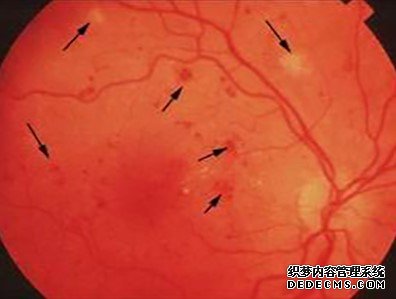

在眼科門診,許多患者主訴眼前有黑影飄動,形態多科多樣,隨著眼球的轉動飄來飄去,飄忽不定,臨床上把這種癥狀稱為“飛蚊癥”,分生理性和病理性兩種。(1)生理性“飛蚊癥&...

玻璃體是充滿眼球后4/5空腔內的透明凝膠體,它像玻璃-樣透明,像雞蛋清一樣黏稠,含水98%~99%,其余為少量透明質酸和黏多糖,無血管、無神經分布,無新陳代謝與新生作用,損失后則留有空腔被房水填充。玻...